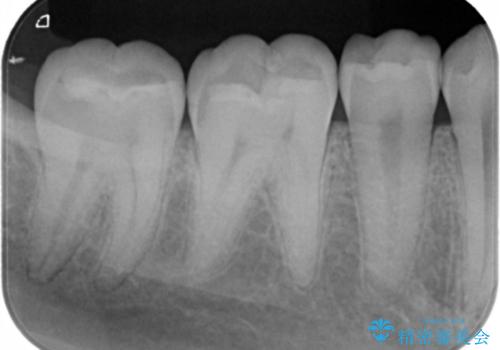

- 右下6・7番の虫歯治療を主訴に来院された患者様です。

精度が高く見た目が良いものを希望されたので、切削量・形態を考慮しセラミックインレーでの治療を計画しました。